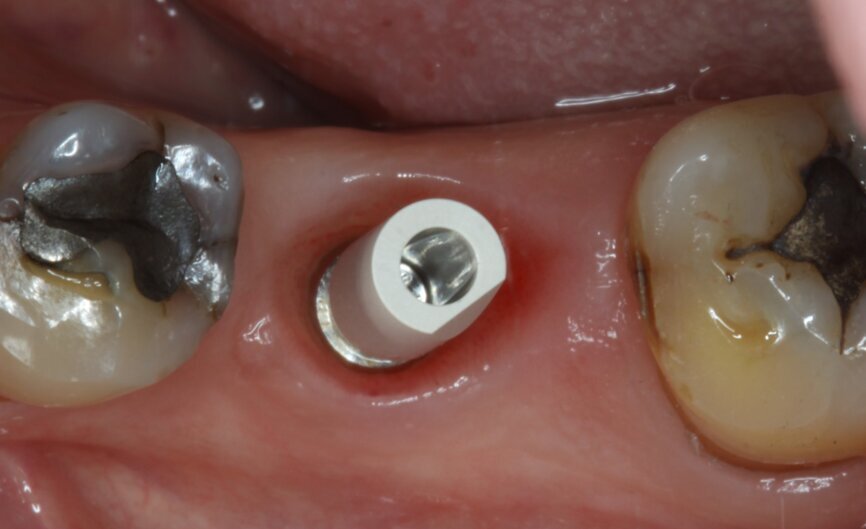

Fig. 1: Intra-oral occlusal view.

Fig. 5: Socket dimensions preserved.